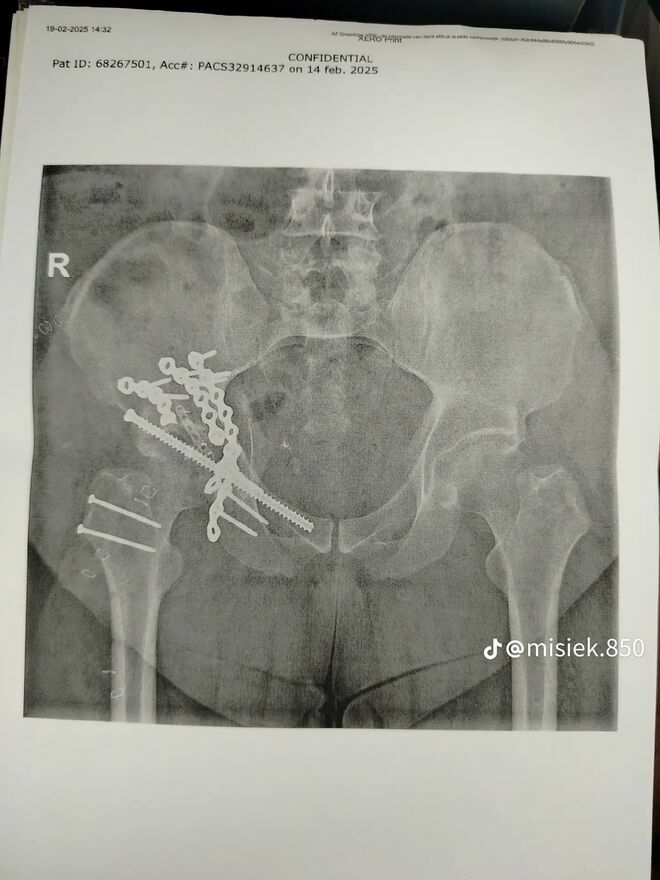

Niestety, jako pasażer uczestniczyłem w bardzo ciężkim wypadku samochodowym, który pozostawił mnie z poważnymi obrażeniami. Leczenie i rehabilitacja są kluczowe dla mojego powrotu do zdrowia, ale wiążą się z wysokimi kosztami, które przekraczają moje możliwości finansowe.